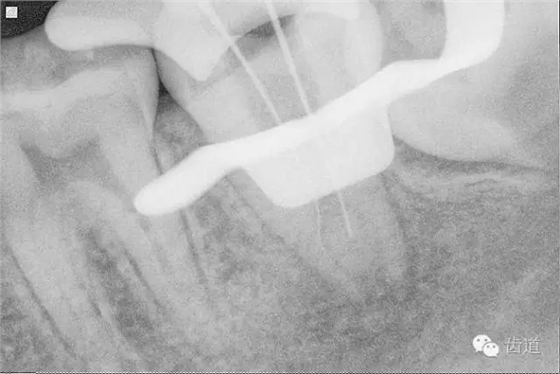

9. 預(yù)彎初尖銼探入根管

10. X線根尖片示尖 (近中及峽部)

11. 探入近中跟及峽部